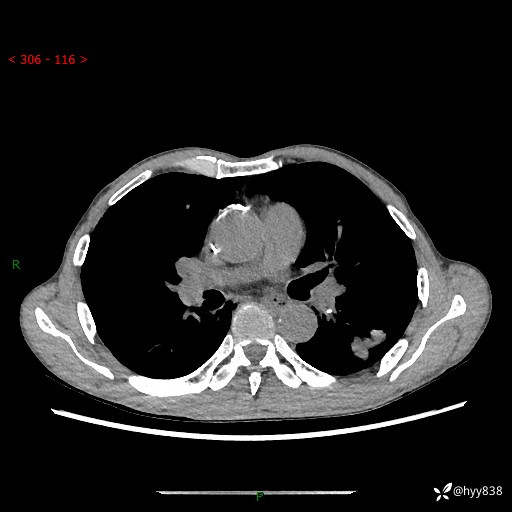

现病史:患者于1月余前无明显诱因出现背部疼痛不适,无明显咳嗽、咳痰、胸闷、咯血、发热等不适,后于2024.5.3至当地市人民医院行胸部CT示:左肺下叶结块,大小约2.2cm*2.6cm,双肺多发小结节,双肺感染性病变,部分纤维增值灶,慢支并双肺局限性肺气肿,肺大泡,纵隔淋巴结增大并部分钙化,冠脉区及大血管壁钙化,双侧胸膜局限性增厚;后口服莫西沙星2周。2024.6.12复查胸部CT示:左肺下叶结块影形态较前饱满,较大截面范围约2.8cm*2.3cm,边缘可见细短毛刺及分叶,性质待查。现患者为求进一步诊治来我院,门诊以“肺占位”收入我科。 起病来,患者精神、食欲、睡眠尚可,大小便正常,体力体重轻微下降。

胸部CT平扫+增强

各期CT值:48hu 100hu 78hu